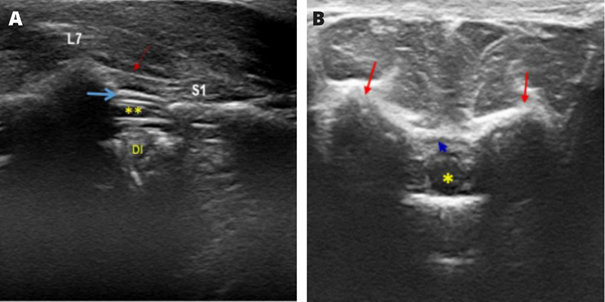

Figure 18 Sonoanatomy of the epidural space in felines.

Caption: (A) Ultrasound image of the structures in the sagittal plane: supraspinatus ligament (red arrow); epidural space (blue arrow); dural sac (**); DI, intervertebral disc; L7, spinous process of the seventh lumbar vertebra; and S1, the first sacral vertebra. (B) Ultrasonographic image of the structures in the transverse plane: dural sac; iliac wings (red arrows), and epidural space (blue arrow).